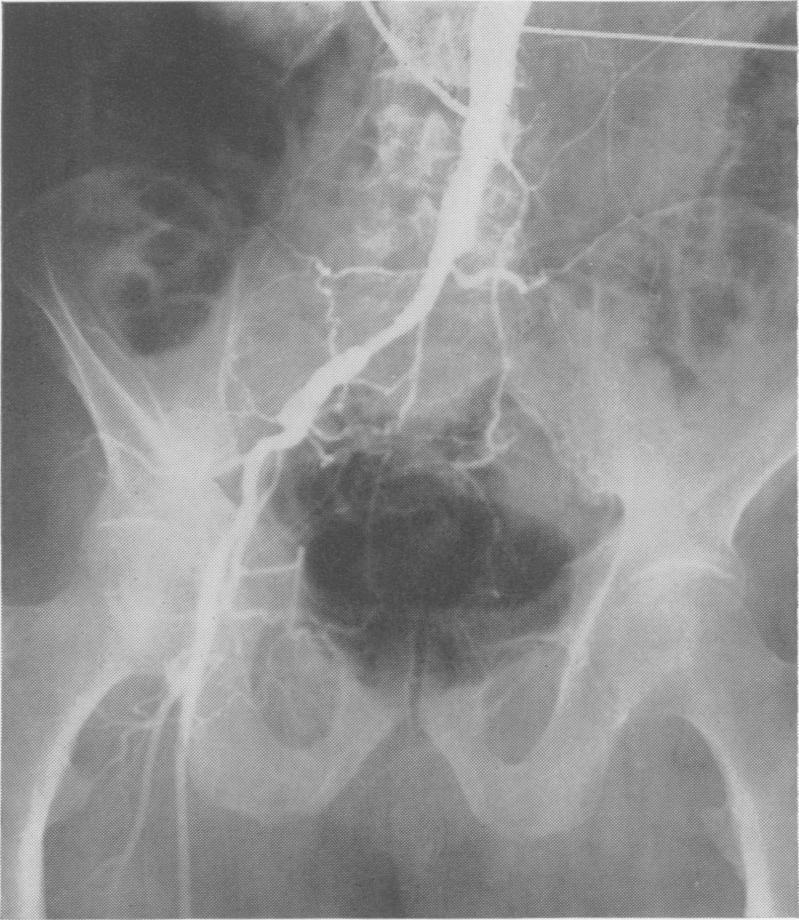

Effect of aortography on renal function.

Ann Surg. 1961 Aug;154(2):190-209. doi: 10.1097/00000658-196108000-00004.

https://cdn.ncbi.nlm.nih.gov/pmc/blobs/33e2/1465880/66683d1f1454/annsurg00856-0055-a.jpg

https://cdn.ncbi.nlm.nih.gov/pmc/blobs/33e2/1465880/aad319368855/annsurg00856-0051-a.jpg

https://cdn.ncbi.nlm.nih.gov/pmc/blobs/33e2/1465880/b8d63753b5a8/annsurg00856-0051-b.jpg